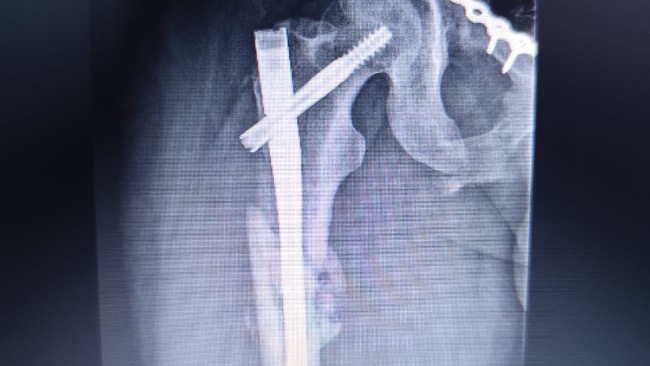

Na miejsce przyleciał śmigłowiec ratunkowy, który zabrał go do szpitala w Olsztynie. Tam rozpoczęła się dramatyczna walka o jego życie. Tata miał zmiażdżone obie nogi, wieloodłamowe złamania obu kości udowych, duży ubytek mięśni i tkanek w lewej nodze, liczne złamania miednicy oraz poważne uszkodzenia narządów wewnętrznych. Lekarze musieli natychmiast operować. Trafił na oddział intensywnej terapii i został wprowadzony w śpiączkę farmakologiczną.

Po ponad miesiącu hospitalizacji tata wrócił do domu, ale jego walka wcale się nie skończyła. Do dziś ma w nodze zewnętrzny stabilizator, metalowy stelaż z prętów wychodzących z uda. Nie jest w stanie samodzielnie chodzić ani ustać na nogach. Porusza się na wózku. Przez długie unieruchomienie jego mięśnie bardzo osłabły, a niektóre zanikły.